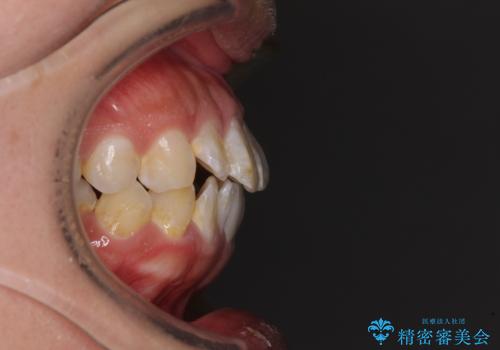

- 前歯のクロスバイトと、口元が閉じにくいとのことで来院された患者様です。

口元の突出感を改善する必要があるため、上下左右の第1小臼歯4本を抜歯し、ワイヤー装置にて矯正治療を行うこととしました。